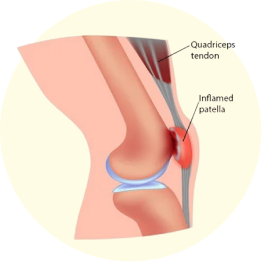

A common condition due to knee pain, where the kneecap (patella) becomes irritated from overuse or misalignment, causing pain around or behind the kneecap, especially during activities like running or climbing stairs.

Both knee (patellar tendonitis) and ankle (Achilles tendonitis) pain can result from tendon inflammation due to overuse or repetitive stress, causing pain, stiffness, and swelling around the affected tendons.